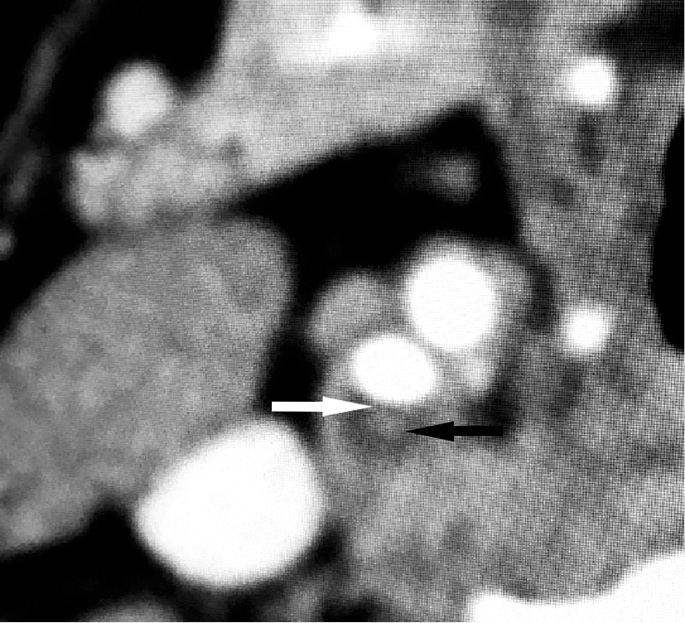

Представление о степени стеноза ВСА и стабильности атеросклеротической бляшки, ее устойчивости к воздействию избыточного давления были получены на основании данных КТ АГ (рис. 6, 7).

Рис. 7. Компьютерная томограмма пациента со стабильной атеросклеротической бляшкой

Fig. 7. Сomputed thomography scan of a patient with a stable atherosclerotic plaque